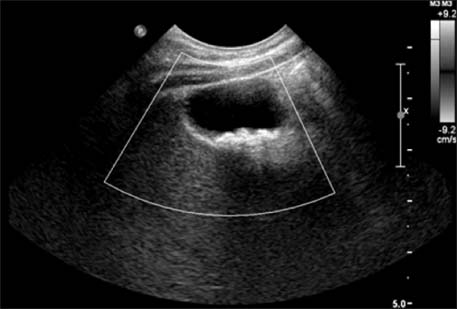

Fig. 3

Ultrasonography after 6 weeks of conservative treatment shows the disappearance of previous gallbladder stones (case 2).

jkaps-20-62-g003.jpg